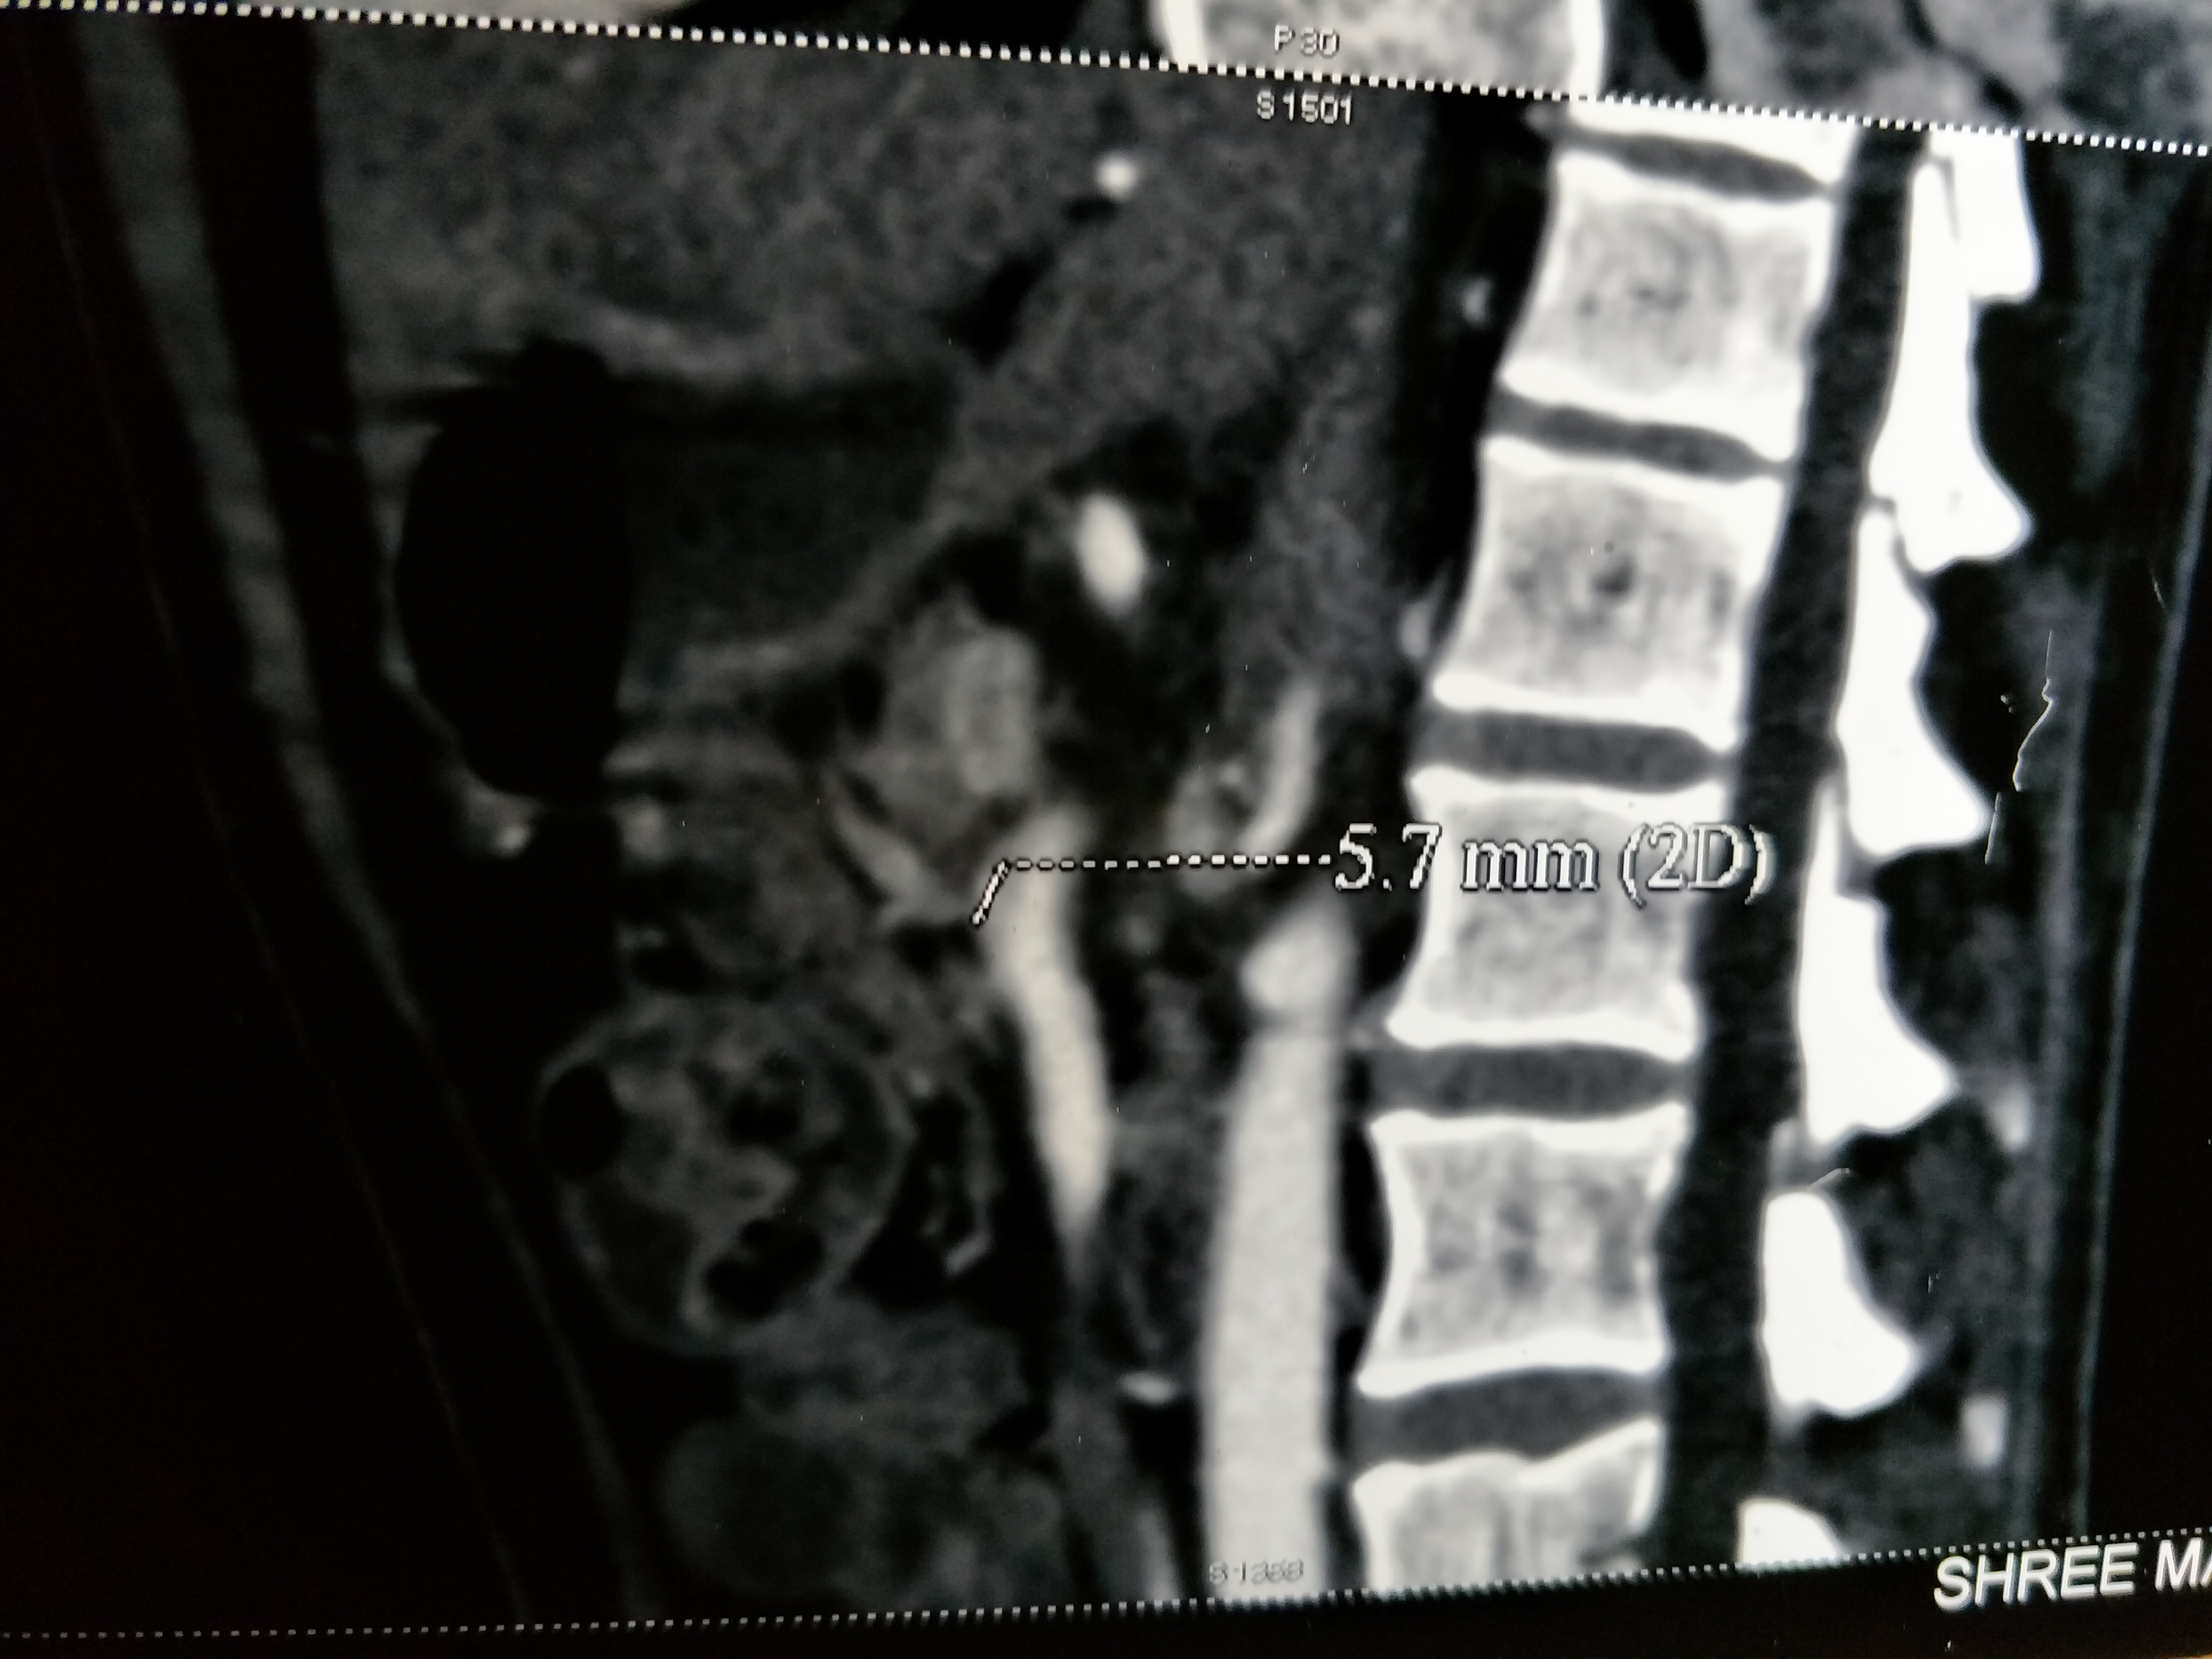

A 30-year-old male patient presented with abdominal pain and vomiting for three days. He was known to be diabetic and presented to the surgical outpatients’ department with the complaint of abdominal pain, on and off for three months. He did not smoke or drink alcohol. There was no history of hematemesis or melena. On physical examination, the temperature was normal, pulse 110/min, respiratory rate 18/min, and blood pressure 140/86 mmHg. Minimal epigastric tenderness was elicited on palpation and bowel sounds were auscultated. Rectal examination was normal. Laboratory findings were normal with a hemoglobin of 14.3g/dL, hematocrit 42%, platelets 425,000/mm3, and white blood cell count 10,000/mm3. Serum analysis revealed the following: random blood sugar, 332mg/dL; aspartate aminotransferase, 24U/L; alanine aminotransferase, 22U/L; and creatinine, 1.0mg/dL. Coagulation profile including PT with INR and aPTT were normal. An ultrasound of the abdomen revealed normal findings. We performed a contrast-enhanced computed tomography scan, which showed a small contrast-filled pouch in the proximal superior mesenteric artery (SMA) (Figure 1,2). However, all other branches showed normal vascularity and the SMA origin was normal. No thrombus was seen within the lumen of the vessel. 3D reconstruction imaging revealed mild enlargement of the SMA with a contrast-filled pouch (Figure 3). We treated the patient conservatively using low molecular weight heparin and tablet aspirin 150 mg daily for anticoagulation. The patient improved and was discharged on warfarin. He was in followed up for six weeks without any problems, and then was lost to follow-up.

Figure 2 Sagittal, contrast-enhanced, arterial phase, maximum intensity projection CT scan shows a contrast filled pouch in the proximal superior mesenteric artery.